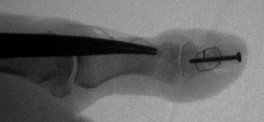

Exploration revealed no discrete  tumor, and a nondiagnostic frozen section. Because of diagnostic uncertainty and in order to avoid intraoperative cross contamination, a cancellous freeze dried allograft was used as a terminal graft:

Click for larger image